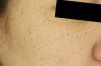

주근깨/흑자(표재성 색소)

표재성 색소란?

주근깨와 흑자는 피부에 나타나는 대표적인 색소 병변으로, 자외선 노출과 유전적 요인이 주요 원인입니다.

주근깨 (Freckles)

• 1주로 10~20대에서 나타나는 표재성 색소 병변으로, 피부 표피층에 위치합니다.

• 2선천적 요인이 강하며, 경계가 뚜렷하고 작은 갈색 점 형태로 나타납니다.

흑자(Lentigo)

• 120~30대 초반에는 표재성 색소로 분류되는 경우가 많으며, 경계가 명확하고 주근깨보다 크고 진한 갈색을 띱니다.

• 2그러나 연령이 높아질수록 진피형 흑자의 가능성이 커지며, 특히 40대 이상이나 출산 후 여성에게서 흔히 나타납니다.

• 3진피형 흑자는 경계가 불분명하고 옅은 갈색 또는 회갈색으로 보이며, 치료가 더 까다로울 수 있습니다.